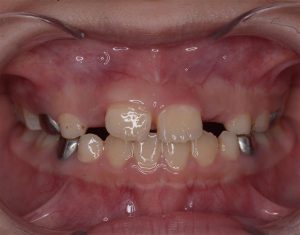

- Khe thưa bất thường: Hai răng cửa chính mọc ra nhưng cách xa nhau (thường >2mm) và không có xu hướng tự khít lại theo thời gian.

- Răng mọc lệch/xoay: Một hoặc cả hai răng cửa bị mọc nghiêng, xoay trục hoặc mọc chìa ra ngoài do bị răng ngầm bên dưới chèn ép.

- Răng vĩnh viễn chậm mọc: Một bên răng cửa đã mọc dài nhưng bên còn lại mãi không thấy “nhú” lên dù đã quá thời gian thay răng.